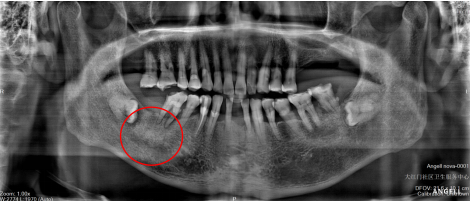

“最开始是我接诊的程爷爷,听到他说已经去过很多家医院都不见好转,心里也很不安,但是看见患者这么不舒服,我们抱着试试看的想法进行了检查。”口腔科医生刘一儒说。经过病情询问、口腔、血项等一系列检查及诊断,刘医生怀疑程爷爷是因“阻生齿”而引起肿胀,拔除右侧牙齿大概率能解决问题。

一般通过口腔检查和 X 光片可以明确。如果发现有阻生齿,应根据具体情况决定处理方式。如果阻生齿没有任何症状,且位置相对较好,医生可能会建议观察。但如果阻生齿经常引发炎症、疼痛,或者对相邻牙齿造成损害,通常就需要进行拔除。尤其备孕期女性,更要提前检查智齿情况,以免孕期出现疼痛等问题。